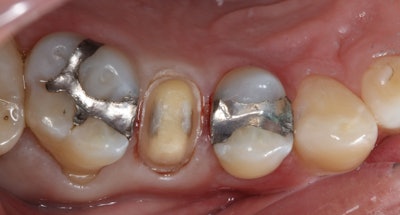

After administering local anesthesia and placing a rubber dam, the existing amalgam restoration was removed and the fracture of the buccal cusp was addressed through controlled reduction. One challenge encountered during the treatment process was the presence of deep caries.

To address this issue, the clinician followed the Fusayama concept of selective caries removal, a well-established protocol from the 1980s. Caries Detector dye guided the removal of infected caries, and the tooth was prepared for a Katana Zirconia One crown, following a 1-mm reduction protocol (Figure 2).

Figure 2.